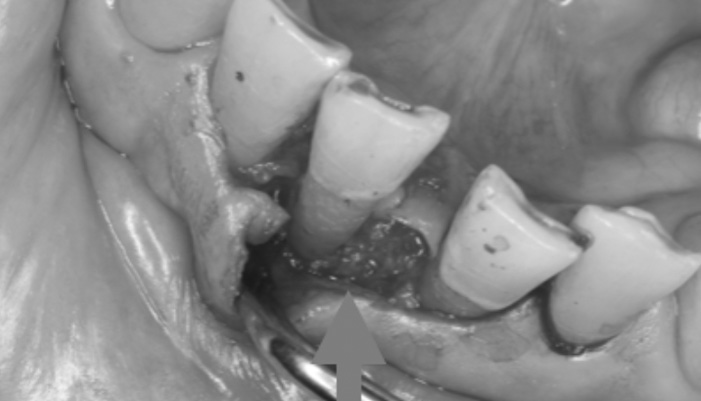

症例1

治療中

治療の経緯

患者様は「他院で神経を取るしかないと言われたが、できれば神経を残したい」とのご希望で来院されました。初診時には冷たいものがしみる症状はありましたが、自発痛や打診痛はなく、診査の結果、歯髄を温存できる可能性があると判断しました。

治療では拡大視野下でむし歯の感染部分を正確に除去し、MTAを用いた歯髄温存療法を実施しました。

| 主訴 | 歯に穴が空いた |

|---|---|

| 治療期間 | 1ヶ月 |

| 治療費 | ¥33,000 |

| 治療内容 | むし歯が大きく、神経を残す治療(歯髄温存療法)を行い、神経を残しダイレクトボンディングにて修復しました。 |

| 治療のリスク | 治療後に痛みが出ることがあります。また、痛みが強くでる場合は神経を取る治療に移行することもあります。 |